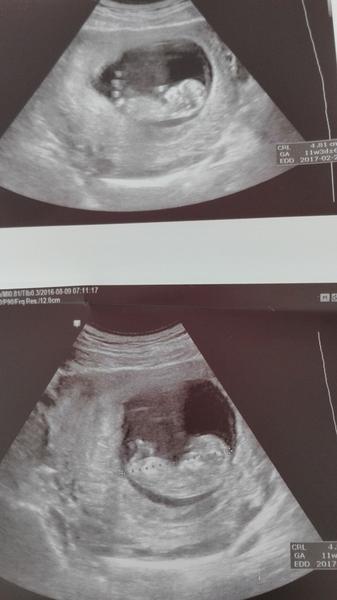

@majamat dakujem baby ale aj vy odpovedate inak,tak ja uz neviem 🙂))) na nete som nasla,ze napriklad NT sa musi robit od 11.-13+6tt max. Potom mozno po tom 15.tt sa robi amniocenteza ale na krvne a ultrazvukove vysetrenie to je po 15.tt dost neskoro ci? Ja len,ze momentalne som v 12.tt a moj lekar mal teraz 2tyzdne dovolenku a dalsiu poradnu mam uz ked budem na zaciatku 13.tt, tak ci to stihnem absolvovat.

Ja budem 12+0 keď pôjdem na ten uzv.